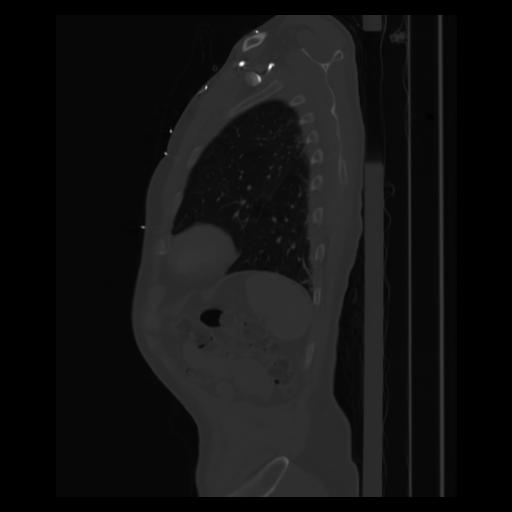

30 CUERPO,CE,Sagittal,3.000,CUERPO,Sagittal,